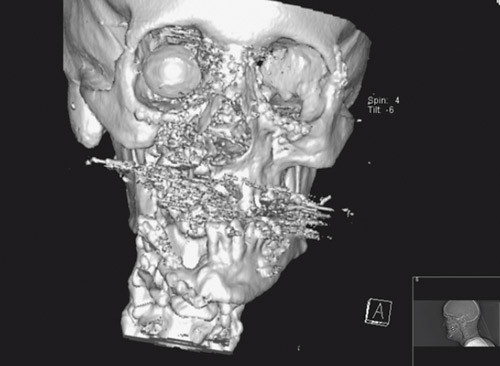

Figur 1 viser avbildning med digital volumtomografi av en pasient med skuddskader etter innsetting av en stor mengde osteosyntesemateriale. Denne metoden ga en fremstilling uten artefakter, mens tradisjonell CT hadde begrenset nytteverdi pga. metallartefakter og utilfredsstillende 3D-modellering (fig 2).